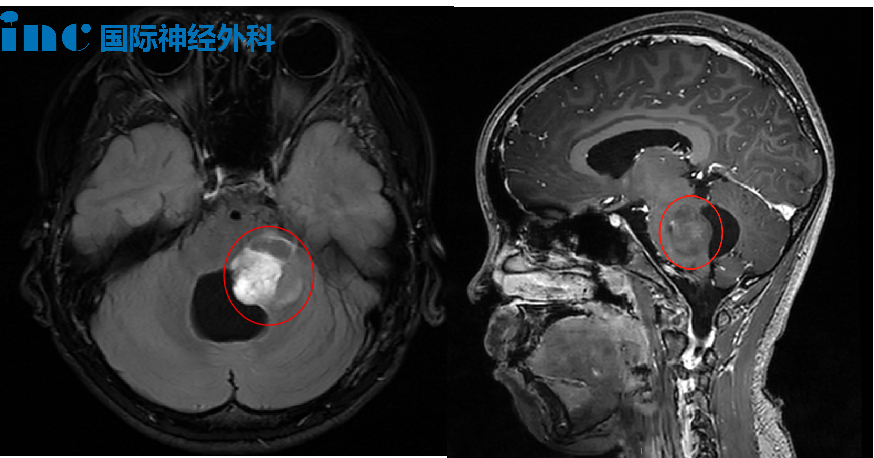

就在剛剛過(guò)去的周末,當(dāng)多數(shù)人享受閑暇時(shí)光時(shí),巴教授仍在為緊急病例進(jìn)行線(xiàn)上咨詢(xún)。你能想象一名6歲半的孩子,已與腦瘤抗?fàn)?年。早在1歲多時(shí),釗釗就被查出腦干占位,但因位置高危、年齡太小,僅進(jìn)行了分流手術(shù)和腫瘤活檢,病理顯示為中分化松果體實(shí)質(zhì)腫瘤。

2025年復(fù)查發(fā)現(xiàn),腫瘤已增長(zhǎng)至4.0×2.8×3.1cm,占據(jù)中腦背側(cè)及腦橋上段,覆蓋整個(gè)松果體區(qū)、壓迫小腦、侵襲雙側(cè)丘腦。面對(duì)如此危急的情況,巴教授明確指出:“繼續(xù)觀(guān)察只會(huì)放任腫瘤繼續(xù)進(jìn)展——若體積超出臨界值將不再具備手術(shù)條件!因此延長(zhǎng)觀(guān)察期屬重大決策失誤。”